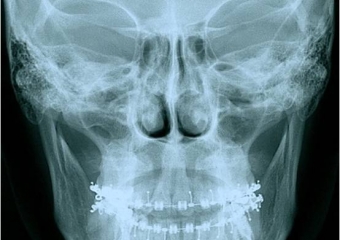

Telerradiografia frontal inicial

Telerradiografia frontal após a cirurgia